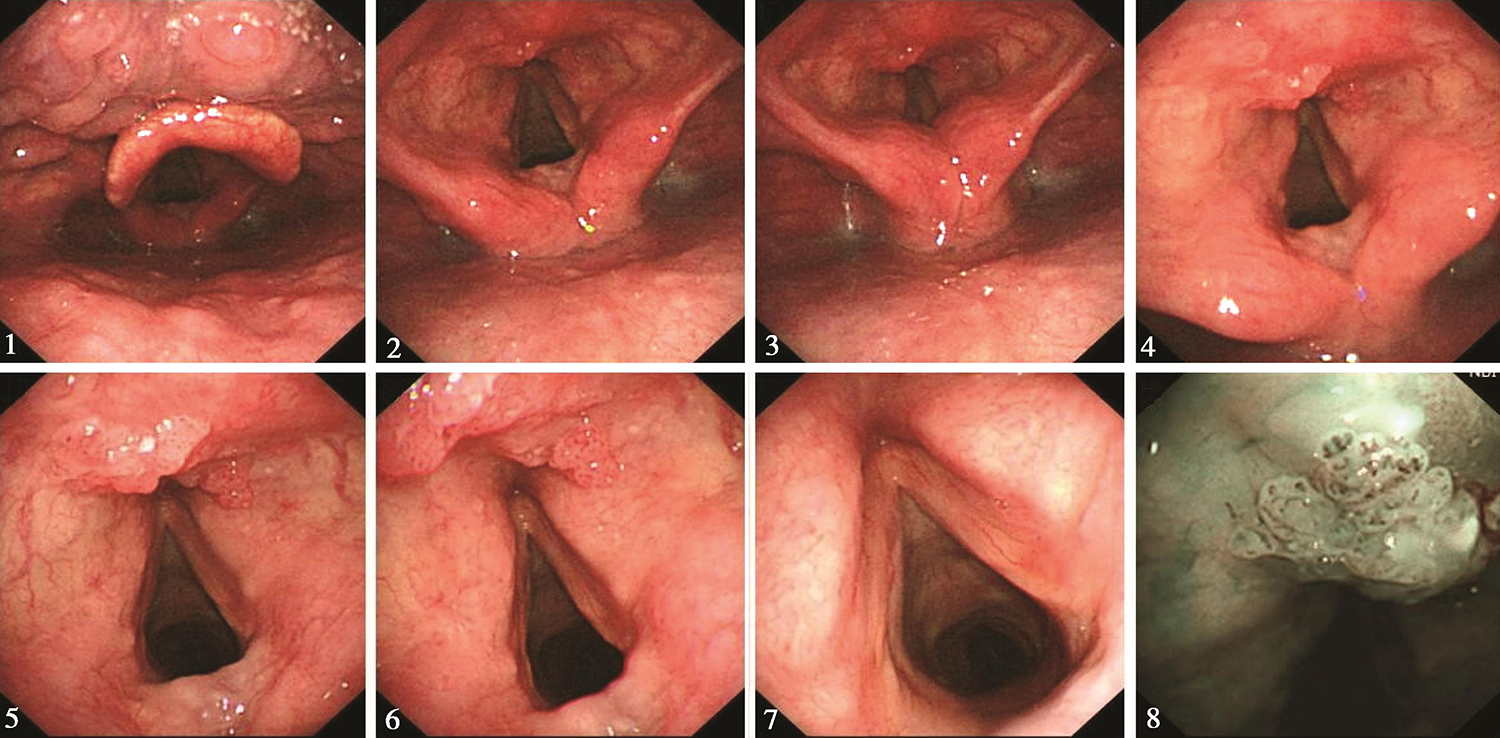

1.2016年11月17日电子内镜检查

鼻腔进镜顺利。鼻咽部结构完整,黏膜光滑,未见明显异常。口咽双侧扁桃体未见肿大。舌根部淋巴滤泡增生。下咽部表面基本平整,未见明显异常。喉部双侧披裂基本对称。会厌根部可见扁平息肉样病变(活检3块),表面呈桑葚样,向下延伸到右侧室带前端(图1)。左侧室带表面尚完整。双侧声带光滑,未见侵及,双侧声带活动正常。

图1 会厌根部不平新生物

内镜诊断:会厌根部肿物(性质待病理检查)。